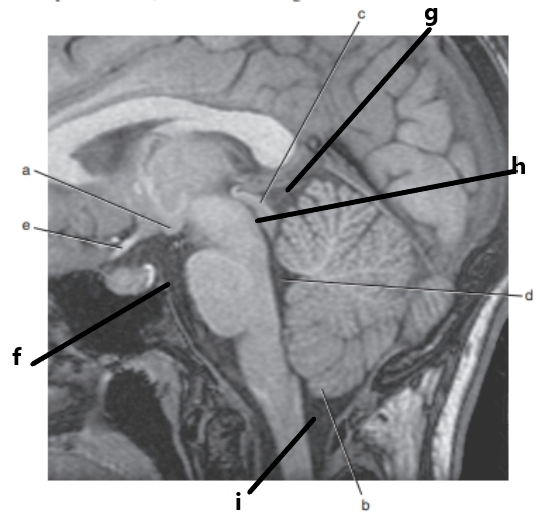

What is h ?

vestibulocochlear nerve

What is g ?

spinal cord

c and d are inside what structure ?

internal auditory canal

Which letter is the superior sagittal sinus ?

a

What is letter h ?

cerebral aqueduct